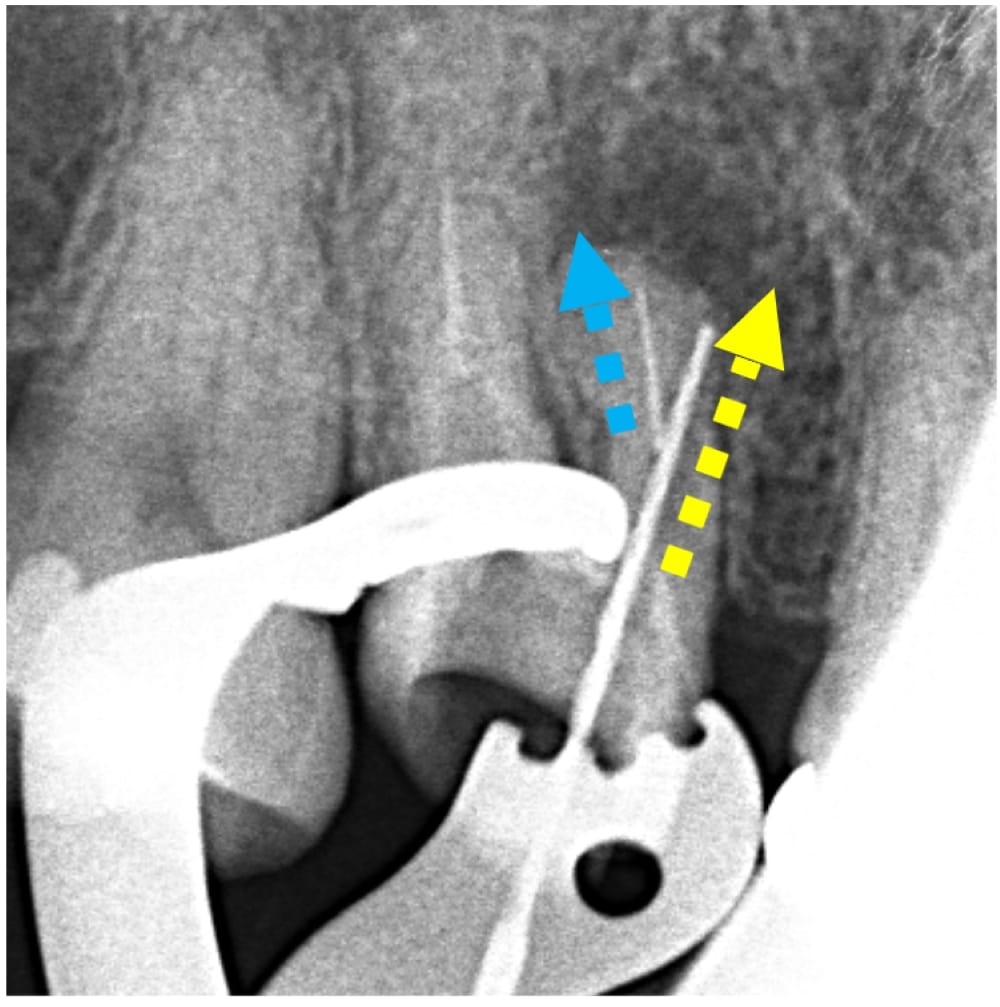

根管内を探索してすぐに、根の中のパーフォレーションが認められました。パーフォレーションとは、歯の本来の根管の方向とは異なる位置に穴があいてしまう偶発症です。おそらく、破折ファイルが起こっていることに気付かぬまま器具操作を行い、根管の中を突き抜けてしまったと推測されます。

(青:本来の根管 黄:パーフォレーション)